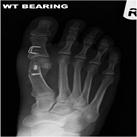

Bunion surgery aims to narrow the often widened forefoot and, thus eliminate or reduce the inner bump. As a result the big toe is straightened and no longer pushes across the lesser toes. The weight-bearing forces are, thus, redistributed, the big toe becomes more functional again and any pain in the ball of the foot (metatarsalgia) may also subside.

Several surgical techniques are available and Mr Weitzel will advise the patient of the most appropriate for her/his individual problem. This will often include a form of osteotomy (cutting and realigning of bone Fig 4) which is then fixed with internal implants such as screws and/or staples.